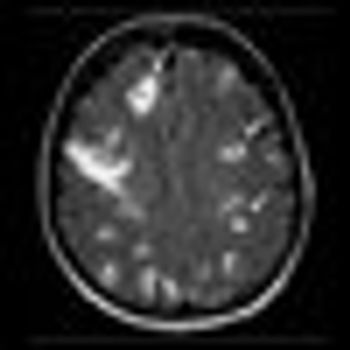

A 13-gene signature can predict the development of brain metastasis among patients with advanced HER2-positive breast cancer who have estrogen-receptor (ER)-negative tumors. The results were presented at a breast cancer session at the 2012 meeting of the American Society of Clinical Oncology.